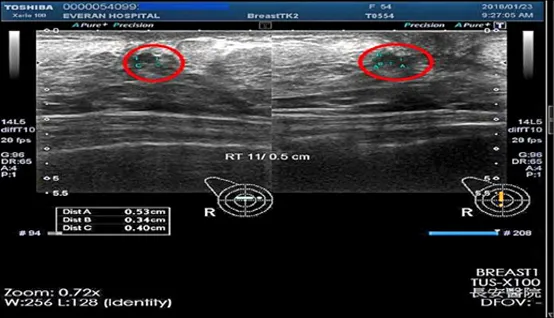

受到體內癌細胞的HER2基因過多影響,腫瘤生長速度快、容易轉移復發的乳癌患者。